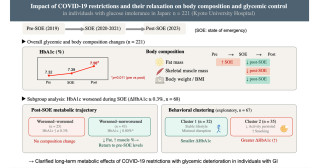

The researchers applied gene therapy for calbindin to one brain hemisphere in nine monkeys to compare the survival rates of dopamine neurons and preference for limbs between the two sides of the body.

Cells in the brain hemisphere that received the gene therapy showed a 50% higher survival rate than the other side, and the monkeys showed a preference for using limbs controlled by the treated hemisphere.

"Neurons positive for proteins that form plaques were more prevalent on the control hemisphere, indicating reduced pathology and reduced Parkinson's symptoms on the treated side of the brain." says Inoue.

MRI images of the coronal and axial planes of the brain. Note the differences in the treated side (right hemisphere) and untreated control side (left hemisphere) (Kyoto University / Takada Lab)